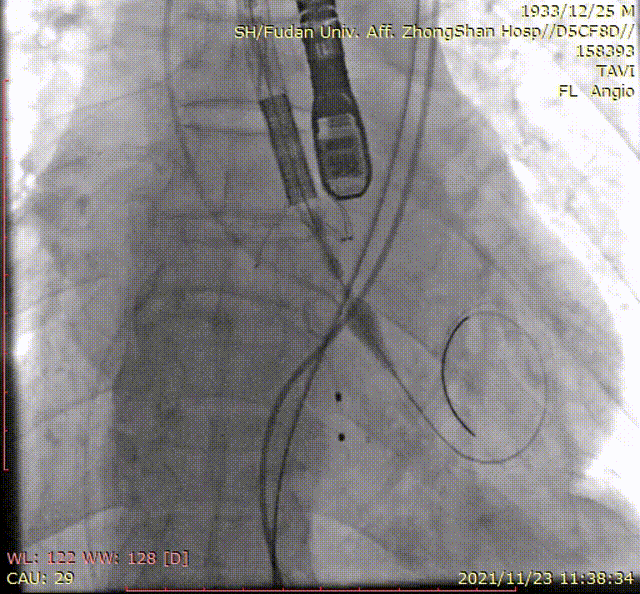

手术过程

术后造影